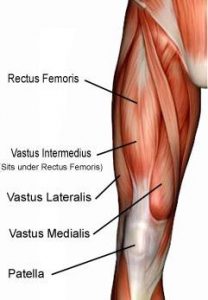

- Quadriceps

Vastus Intermedialis and the third is the Vastus Medialis Oblique. Each of these muscles attaches onto the patella and has its own direction of pull. The VL pulls the knee cap laterally (to the outside), while the VI pulls the knee cap directly upwards. The VMO, meanwhile, pulls the patella medially (to the inside).

Vastus Intermedialis and the third is the Vastus Medialis Oblique. Each of these muscles attaches onto the patella and has its own direction of pull. The VL pulls the knee cap laterally (to the outside), while the VI pulls the knee cap directly upwards. The VMO, meanwhile, pulls the patella medially (to the inside).